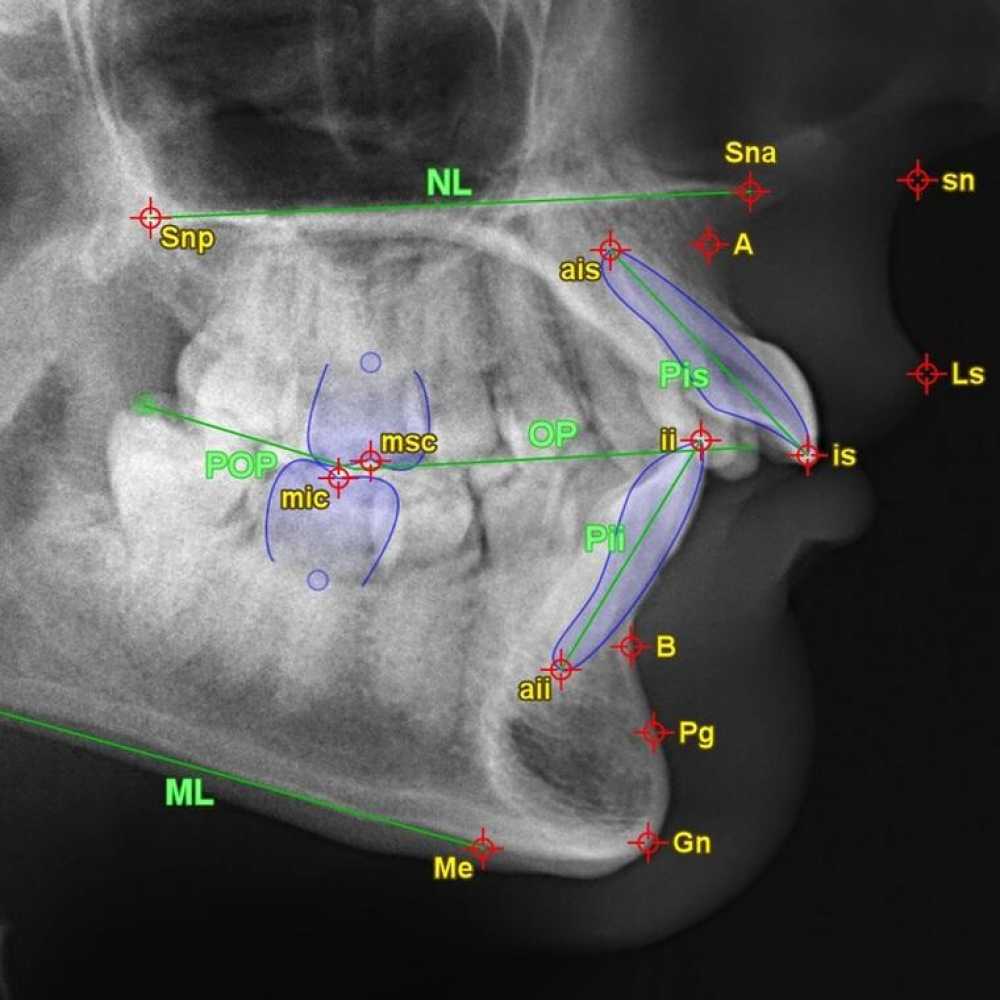

Діагностика в ортодонтії

Лікарська / фармацевтична спеціальність: Ортодонтія, Стоматологія

9:00-13:00 - Теорія:

- огляд основних етапів діагностичного процесу

- аналіз функціональних і структурних порушень

- сучасні методі діагностики

- формування плану лікування

14:00-17:00 - Практика:

- Практичне відпрацювання на моделях